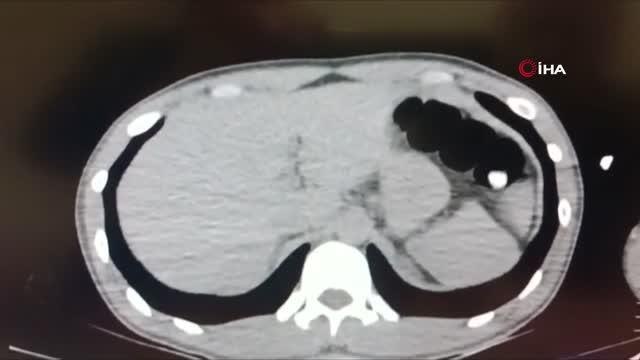

Zanlının bağırsak filmi -Filmde bağırsaklarında yabancı cismin belli olması -Bağırsaklarından çıkanların görüntüsü -Zanlının emniyetten çıkartılması -Adliyeye götürülmesi ( ADANA ) Bağırsağından 47 paket uyuşturucu çıktı haberim yok dedi- Adana'da yakalanan İran uyruklu bir şahsın çekilen tomografisinde bağırsağında 47 paket uyuşturucu olduğu tespit edilip ilaç yöntemiyle 5 gün sonra çıkarıldı- Bağırsağından 116 gram metanfetamin, 104 gram eroin ve 107 gram afyon sakızı çıkan zanlının Van'da beni uyutmuşlardı o zaman koymuş olmalılar haberim yok dediği öğrenildi ADANA - Adana'da yakalanan İran uyruklu bir şahsın çekilen tomografisinde bağırsağında 47 paket uyuşturucu olduğu tespit edilip ilaç yöntemiyle 5 gün sonra çıkarıldı. Zanlınını, Van'da beni uyutmuşlardı o zaman koymuş olmalılar haberim yok demesi dikkat çekti. Adana ve Van Emniyet Müdürlüğü Narkotik Suçlarla Mücadele Şube Müdürlüğü ekiplerinin ortak çalışmasında, İran'dan Van üzerinden Türkiye'ye giriş yapan ve uçakla Adana'ya giden Faramarz Tayefehrostami (52) isimli İran uyruklu şahsın uyuşturucu sevkıyatı yaptığı bilgisine ulaşıldı. Bunun üzerine Adana polisi havalimanında zanlıyı beklemeye başladı. Van-Adana uçağı havalimanına iniş yapınca zanlı polis tarafından gözaltına alındı. Zanlı emniyete getirilerek sorguya alındı. Polis yaptığı bagaj ve üst aramasında uyuşturucuya rastlamadı. Bunun üzerine polis zanlının uyuşturucu yutma yöntemiyle taşıyacağını düşünerek zanlıya bu yöntemi kullanıp kullanmadığını sordu ancak zanlı bunu inkar etti. Polis bunun üzerine savcılıktan alınan izinle zanlıyı Çukurova Üniversitesi Tıp Fakültesi Balcalı Hastanesi Gastroenteroloji Bölümüne götürdü. Burada zanlının bağırsak tomografisi çekildi. Zanlının bağırsaklarında serçe parmağı büyüklüğünde yabancı cisimler olduğu tespit edildi. Buna rağmen zanlı uyuşturucu olmadığını ileri sürmeye devam etti. Doktorlar zanlıya özel bir ilaç vererek bağırsaklarında yabancı cisimlerin tuvalet yoluyla çıkmasını sağladı. 5 günün sonunda zanlının bağırsaklarından 4 pakette 116 gram metamfetamin, 21 pakette 104 gram eroin, 22 pakette 107 gram afyon sakızı çıktı. Zanlının uyuşturucular çıktıktan sonra ifade değiştirip, Van'da beni uyutmuşlardı o zaman koymuş olabilirler ne yaptıklarını bilmiyorum benim haberim yok dediği öğrenildi. Zanlı ifadesi alındıktan sonra adliyeye sevk edildi. Adana'da 21 Aralık 2019 günü de yine havalimanında, Van'dan gelen İran uyruklu Seddigh Raşhıdıtavana (58) isimli şahsın bağırsaklarından 49 pakette 765 gram eroin çıkmıştı. (FKE- beyazgazete.com/video/webtv/guncel-1/bagirsagindan-47-paket-uyusturucu-cikti-haberim-yok-dedi-811217.html</a>